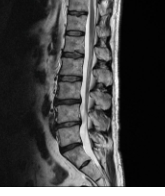

3. 척추관 협착증

척추관 협착증은 척추의 중앙에 있는 관이 좁아져서 신경이 압박되는 상태를 말합니다. 척추관 협착증은 나이가 들면서 척추의 변성이나 염증으로 인해 발생할 수 있습니다. 척추관 협착증은 허리와 다리에 통증이 생기고, 걷거나 서있는 것이 어려워집니다. 척추관 협착증은 보통 약물 치료나 물리 치료로 증상을 완화할 수 있지만, 심한 경우에는 수술이 필요할 수 있습니다.